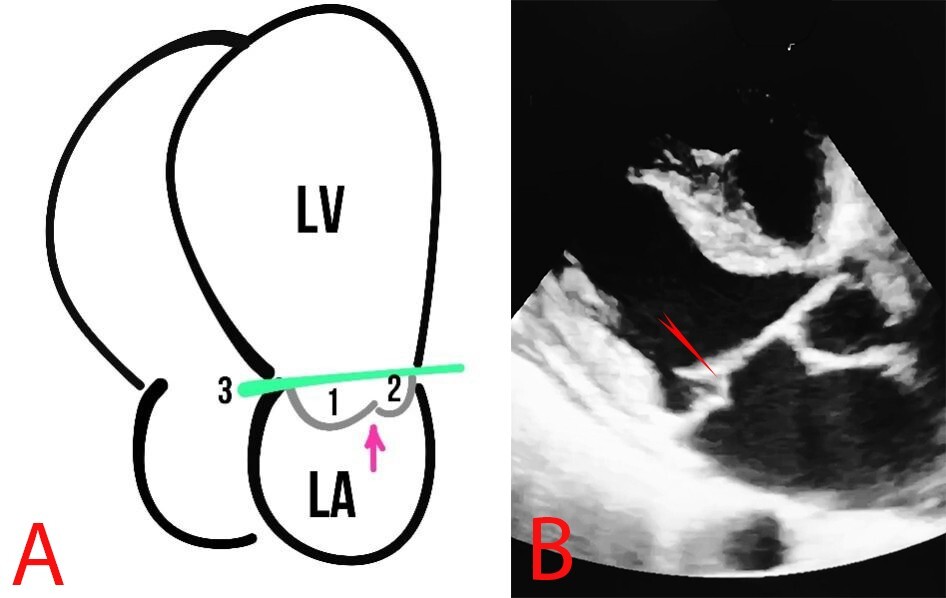

The structure and function of the MV leaflets are evaluated polypositionally using different modes, such as M-mode, B-mode, and Color Doppler mode. Normally, the mitral annulus has a curved shape and a saddle-shaped bend in the sagittal plane (Fig. 3).

Fig. 3. Schematic presentation (A) and echocardiography (B) of normal findings. (A) The numbers 1 and 2 show the mitral valve flaps, the line (3) shows the mitral annulus, and the arrow indicates the coaptation zone. LA, left atrium.